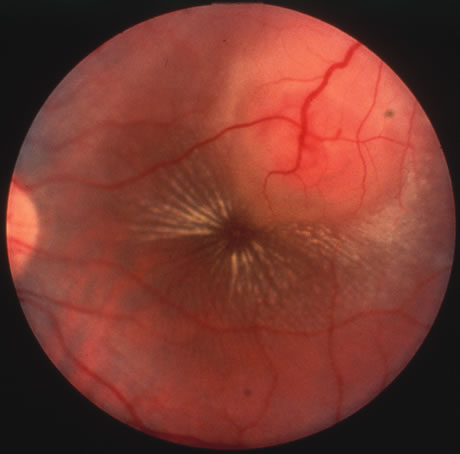

The acute retinal necrosis (ARN) syndrome is most often caused by the herpes zoster virus, although occasionally it may be a result of herpes simplex infection.12 It is typically described in healthy patients although association with immunosuppressed patients has also been described. Granular, nonhemorrhagic areas of retinal necrosis may be observed in the fundus, often rapidly coalescing with resulting blindness often caused by retinal detachment. There is often an associated vasculitis and vitritis. In immunocompromised patients VZV or HSV retinitis may also take the pattern of progressive outer retinal necrosis (PORN) (Fig. 6). PORN differs from ARN in that the former is multifocal, localized to the outer retina, and is less often associated with vasculitis and vitritis.

Fig. 6. Fundus lesions of progressive outer retinal necrosis (PORN). Note the multifocal lesions.